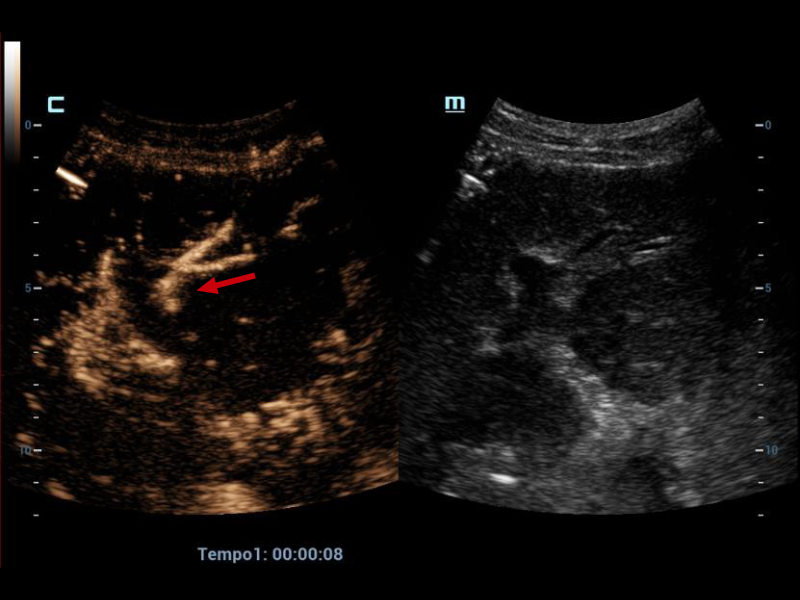

Therefore, it was decided to continue the assessment with contrasted ultrasound, an enhancement of vascular structures (Figures 2 and 3) can be observed about 8 seconds from the hepatic artery and 17 seconds from the portal vein without finding filling defects or areas of stenosis, however, in the portal phase of hepatic enhancement an area of hypoperfusion in segments 7/8, evidenced both by the live image and in the post-process of the perfusion curves and maps, this area was triangular morphology and subcapsular location (Figure 4), as well as the right hepatic artery is not visualized by this method, and the left was located at the level of the portal "H"(Figure 5).

Left hepatic artery with adequate opacification (red arrow).

Figure 5. Left hepatic artery with adequate opacification (red arrow).